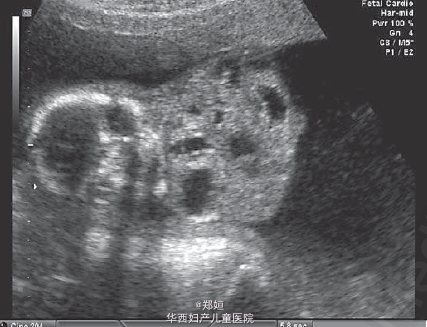

19岁初产妇,孕18周因超声提示胎儿异常就诊

超声和多普勒提示胎儿颈部有一无血流的复杂性多囊肿块 羊膜腔穿刺和流式细胞学均提示无遗传学异常